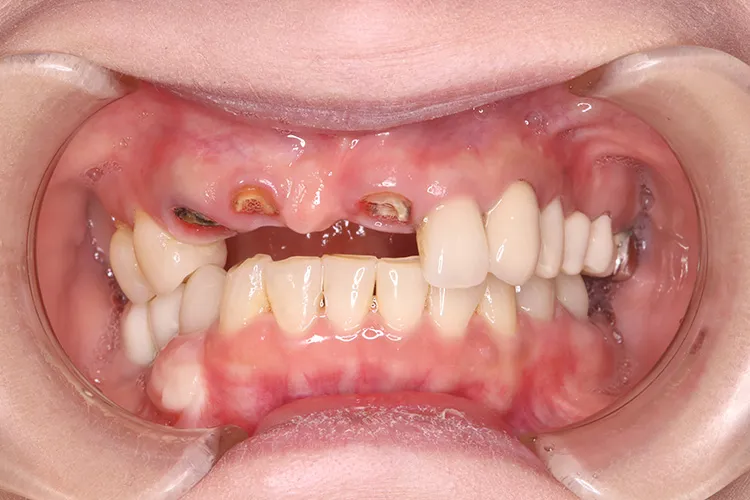

前歯の古いブリッジが脱離し、土台となっていた3本の歯も傷みがはげしく再度のブリッジ治療が不可能な状態でした。前歯ということで欠損を放置できないため、抜歯と同時にインプラントを3本埋入し即日で仮歯までいれました。治療期間中、見た目を気にすることなくオペから4ヶ月で最終のジルコニア4本ブリッジを装着し治療完了しました。抜歯即時埋入は術後の痛みもほとんどなく、治療期間の短縮や患者様の負担軽減などメリットの大きい治療法です。